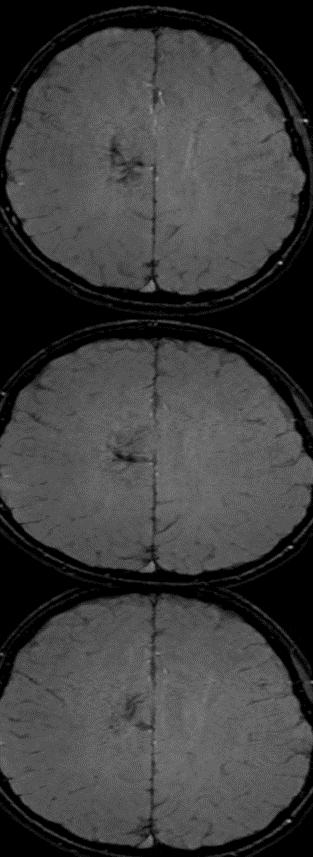

男患,12岁,发作性四肢无力,再发3天。主要表现:无明显诱因四肢无力,双下肢不能抬起,双上肢可抬起,但不能持物,持续约3小时后自行缓解,缓解期无不适。

答案: 静脉畸形(venous malformation),也称为脑发育性静脉畸形(cerebral developmental venous anomalies)

这个比较考眼力:DWI可见端倪, 箭头处为引流静脉。

脑发育性静脉畸形是最常见的脑血管畸形。常在CT、核磁检查时偶然发现。多数情况下为良性病程,个别情况下可伴临床症状,包括癫痫、局灶性神经功能障碍如运动感觉障碍、头痛、引起颅内出血相关症状等。可伴其他血管畸形,最常见的为海绵状血管瘤(12%-40%)。

典型征象:水母头征,由很多较细的髓静脉组成,这些髓静脉的血液汇入较粗的引流静脉。SWI和CT/MRI增强扫描尤为明显,其他核磁序列和CT平扫亦有可能显示。